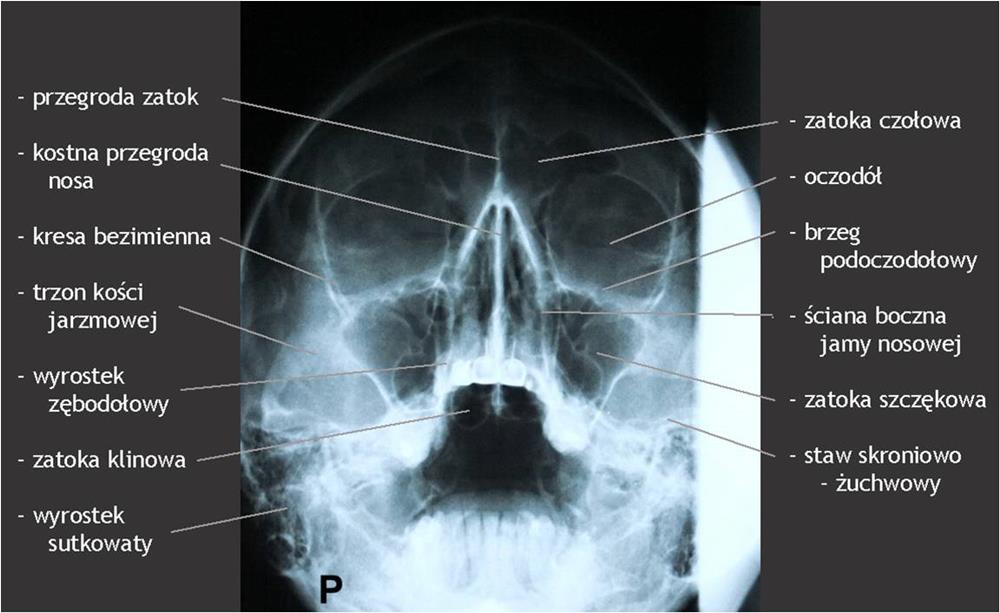

Zatoki oboczne nosa są pneumatycznymi przestrzeniami w kościach części twarzowej czaszki połączonymi z jamą nosową. Zatoki biorą czynny udział w wymianie gazowej, ogrzewają i nawilżają powietrze wydychane przez nos, wytwarzają rezonans dźwiękowy oraz pełnią funkcje ochronne.

Diagnostyka obrazowa zatok staje się coraz bardziej istotna dla lekarzy dentystów, którzy posiadają w swoich gabinetach aparaty tomografii stożkowej (CBCT). W zależności od wielkości pola obrazowania w CBCT są widoczne fragmenty zatok szczękowych aż po całe zatoki szczękowe, a w badaniach o największym polu obrazowania wszystkie zatoki oboczne nosa, podobnie jak w badaniu medycznej tomografii komputerowej (TK). Z tego względu celem pracy jest przedstawienie najważniejszych zmian patologicznych zatok szczękowych, z którymi może się spotkać lekarz stomatolog, opisując badania tomografii stożkowej (CBCT).